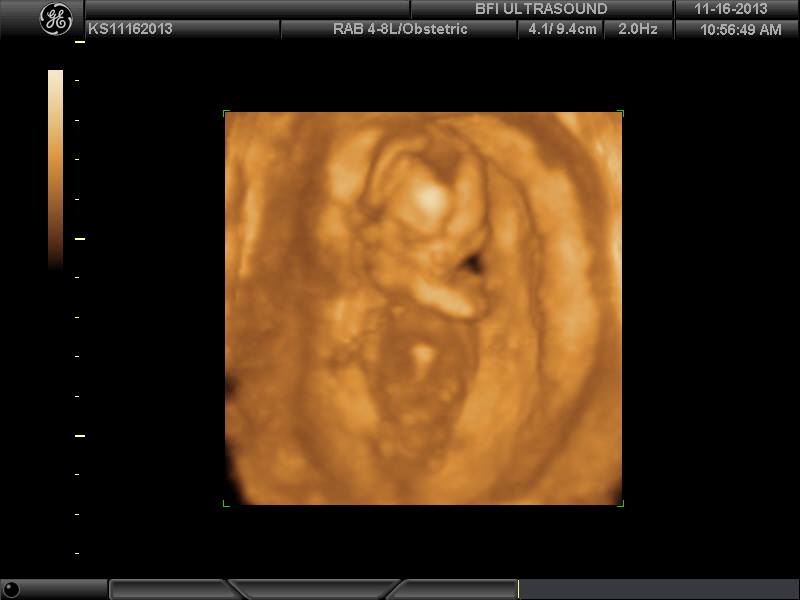

BFP#4 8.27.13 (EDD 5.6.14) DD born 4.23.14